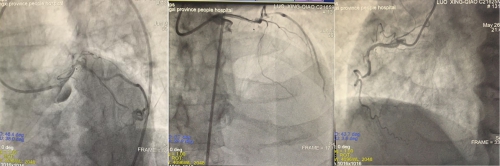

术后造影:左主干至回旋支狭窄消失,右冠成功开通,血流TiMi 3级

6月4日,在省心血管病医院院长洪浪的指导下,李林锋团队为患者进行了介入治疗手术。正如预计的一样,介入导丝通过“罪犯”血管左主干回旋支,患者就出现血压、心率下降,立即给予多巴胺升压,阿托品提升心率,IABP支持,经导丝快速送入球囊扩张病变,恢复血流,待患者生命体征平稳后,快速行回旋支-左主干支架植入术,手术惊心动魄,就像钢丝上的行走。做好了回旋支至左主干病变后,尝试开通前降支失败,是否要去尝试一下右冠呢?再次征求了患者及家属意见,为了远期预后,希望开通右冠脉闭塞病变,患者的信任和希望,再次给了手术团队的信心,手术团队在不到1小时内成功处理好了右冠闭塞病变。